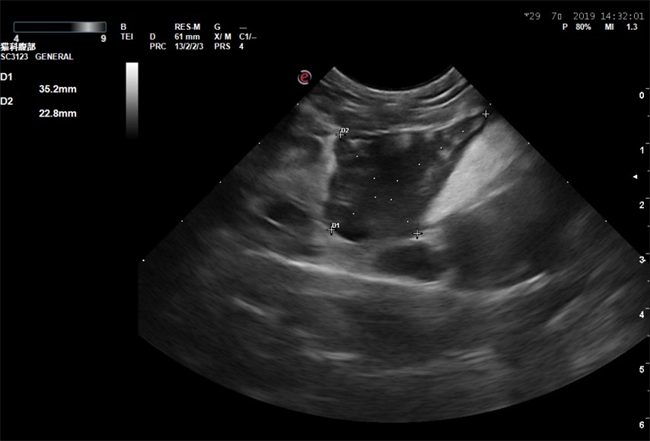

3.7 超声检查结果

超声显示:胸腔积液,心脏头侧纵隔处有一3.5cm*2.28cm大小低回声团块,心脏超声未见明显异常,腹部超声未见积液,未见异常。